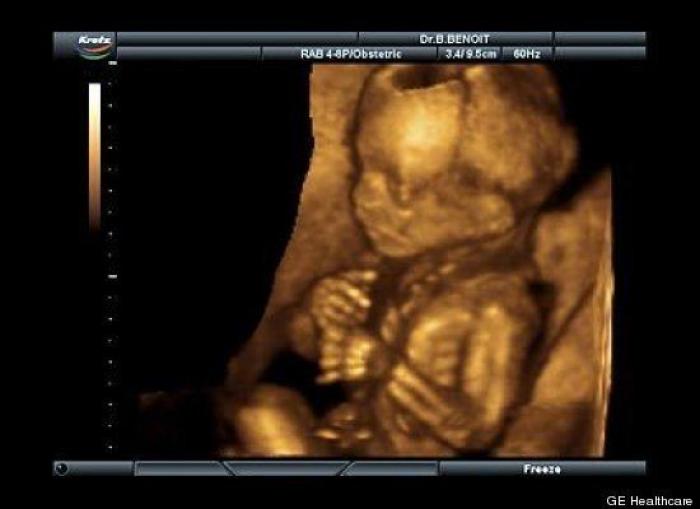

En esta galería puedes ver en fotos como es el desarrollo de un feto de semana en semana:

Desarrollo del feto, en fotos

Ver la galería